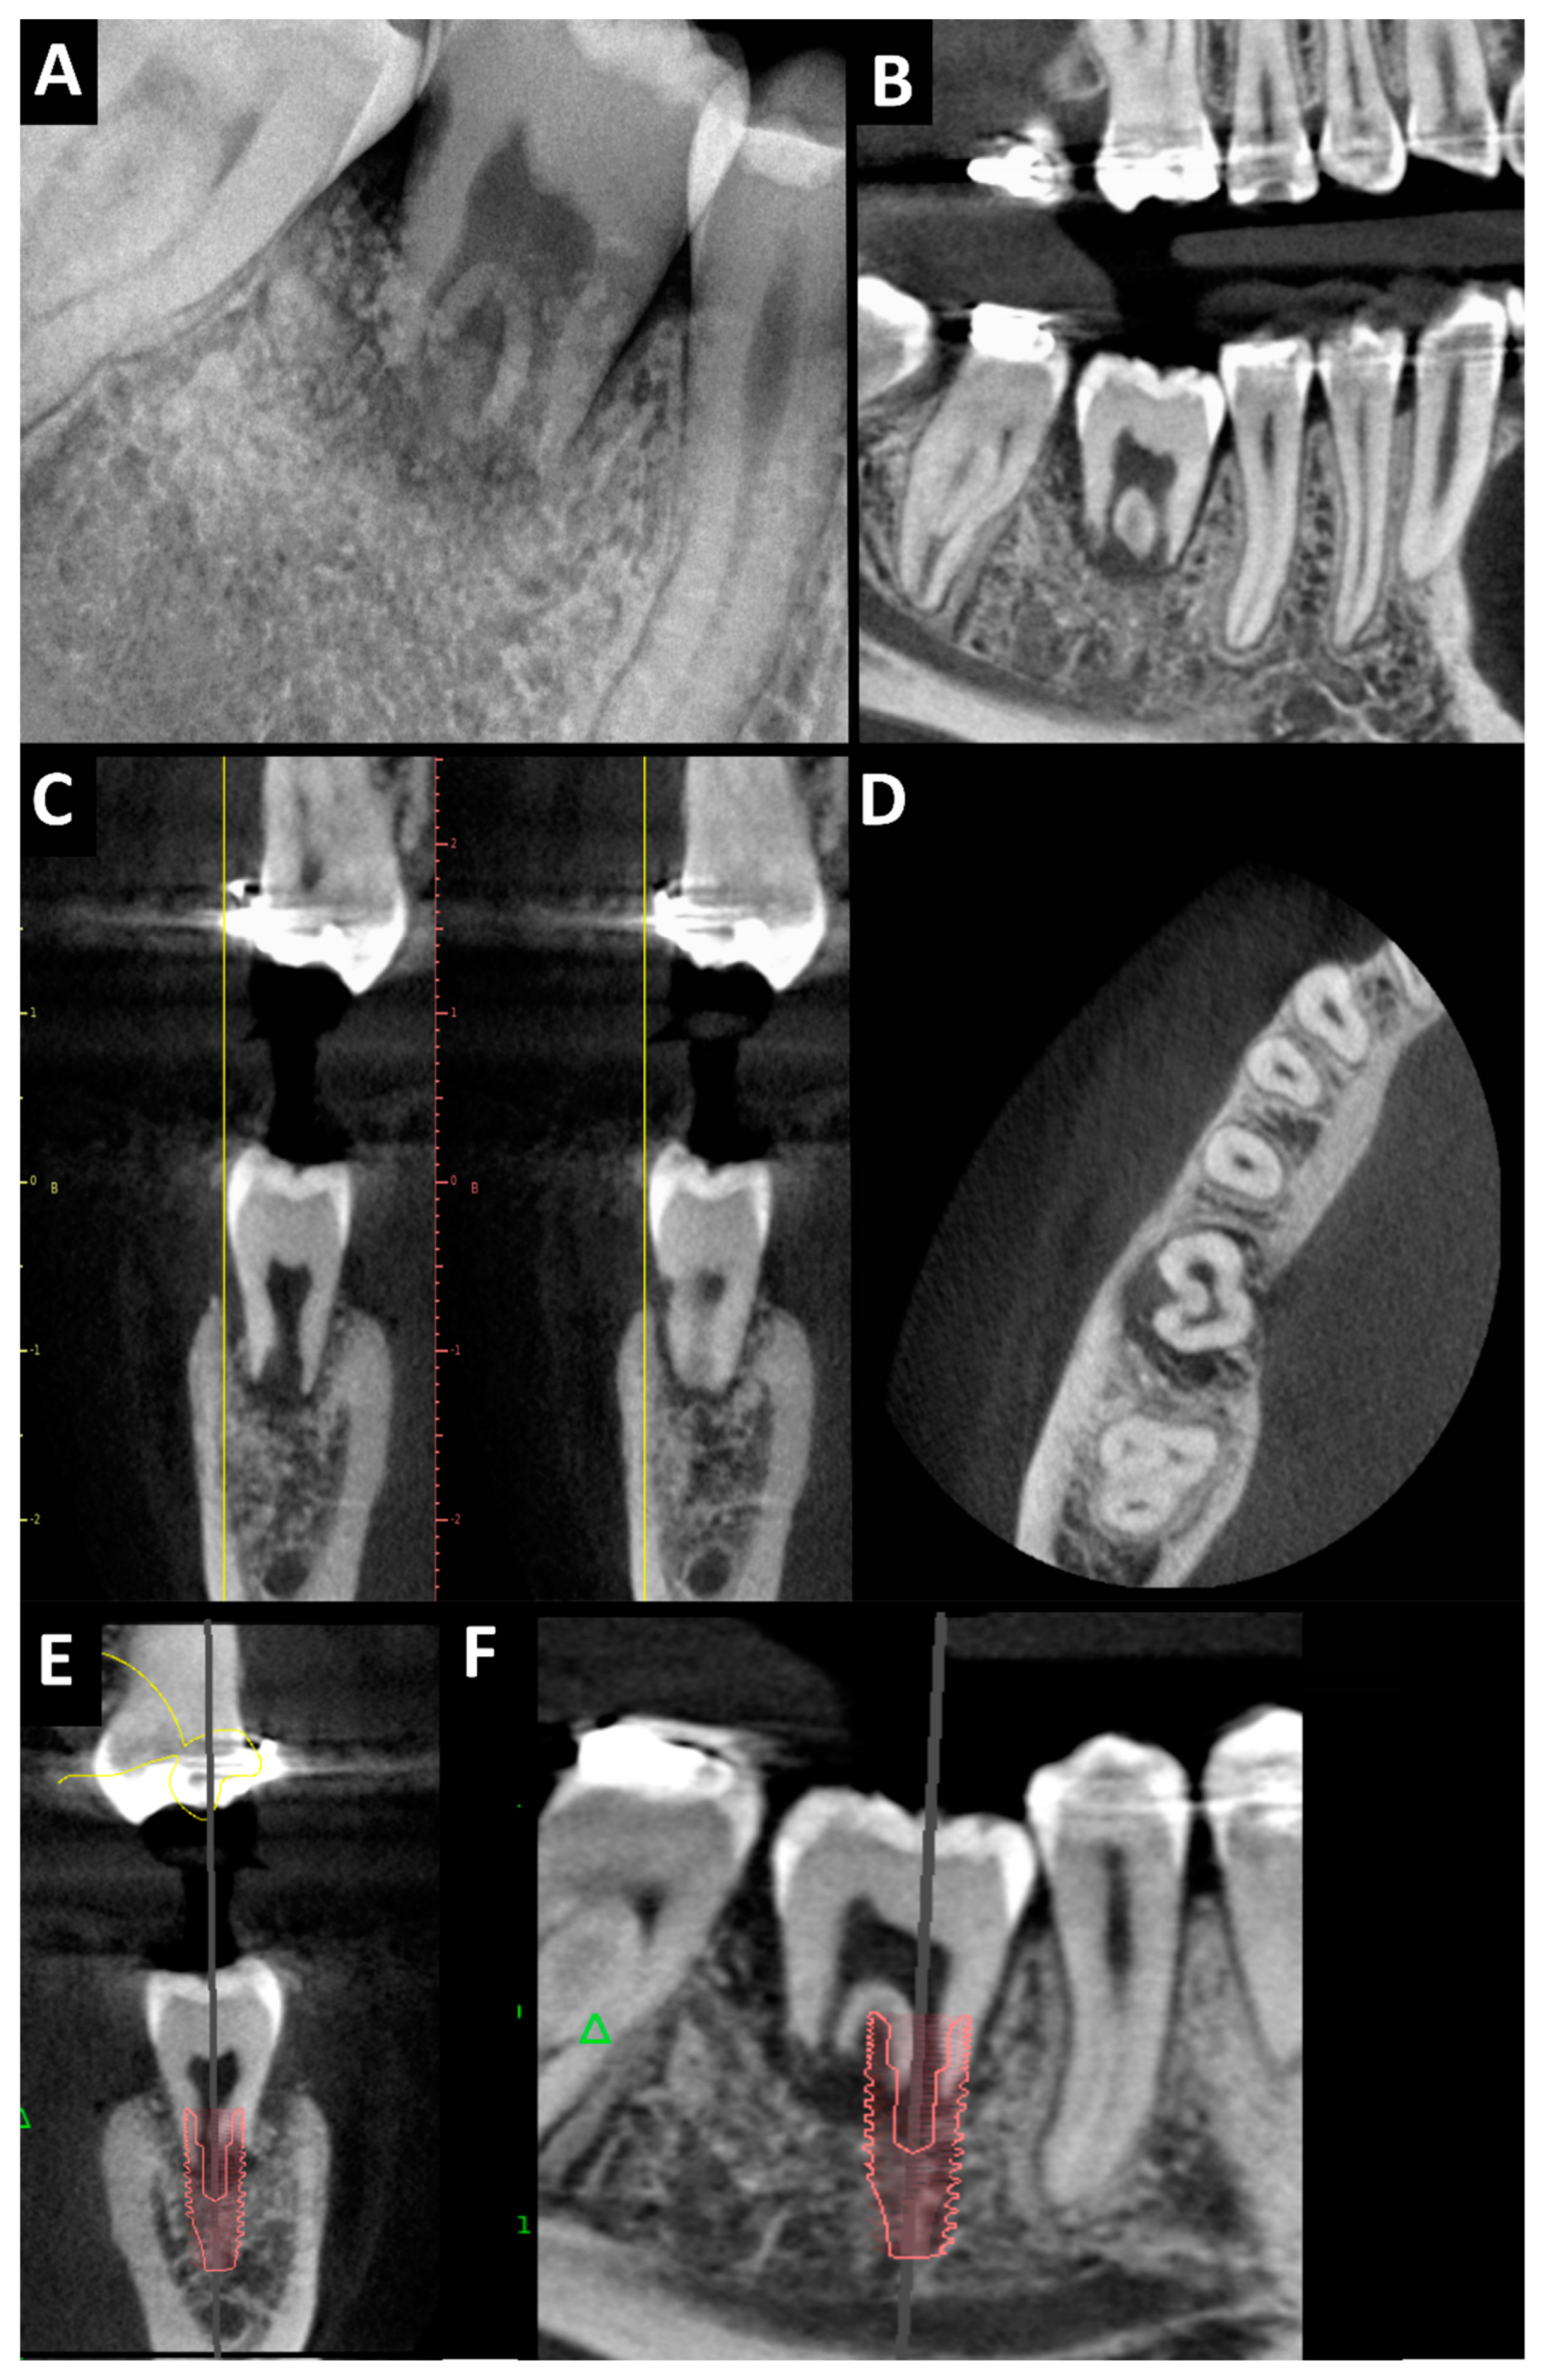

Figure 4.

Pulp necrosis and reconstruction of the bone defect—diagnostic imaging one year after the surgical procedure showing cervical inflammatory resorption, unchanged pulp canal dimensions, absent root growth, periapical radiolucency, lack of apical and marginal healing, obtaining interproximal bone with its normal level, and bone presence at the labial and lingual side of the transplanted molar: (A) dental X-ray—tooth no. 38 in place of tooth no. 46; CBCT after 1 year—tooth no. 38 in place of tooth no. 46; (B–D): (B) pantomography reconstruction; (C) cross-sectional view; (D) axial view—visible bone healing; implant planning (E,F): (E) cross-sectional view; (F) orthopantomography reconstruction (planed implant: ø 4.2 mm, H 13 mm).

After one year, in the clinical examination, there were no signs of inflammation of the soft tissues. The PTV value was +11. Periodontal pocket measurements showed mesiobuccal depths of 3 mm, mesiolingual depths of 3 mm, distal–buccal depths of 4 mm, and distal–lingual depths of 7 mm. A dental X-ray and CBCT were performed (Figure 4A–D) and showed cervical inflammatory resorption, unchanged pulp canal dimensions, absent root growth, periapical radiolucency, and a lack of apical and marginal healing. Due to the pulp necrosis with mobility of the tooth and the presence of resorption, we did not perform root canal treatment of the tooth as an attempt to treat resorption. The tooth was qualified for extraction with immediate implantation. The width and height of the alveolar part of the mandible were correct, and the mesiodistal space between teeth nos. 45 and 47 was preserved, as well as the bone peaks and papillae at teeth nos. 45 and 47 (Figure 4E,F). For this patient, predictable immediate implant placement could have been performed. The patient did not consent to the proposed treatment. Due to the patient’s lack of consent to implant treatment, the transplanted tooth was removed. Healing was good, without complications.